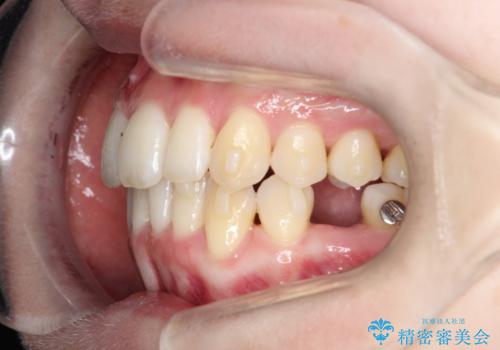

- 患者様は、前歯のガタガタ(叢生)と左下5番の欠損部が気になるとのことで来院されました。診断の結果、インビザラインを用いて前歯の叢生を整えながら、左下5番の欠損部にはインプラント治療を計画しました。矯正治療により、歯並びを改善すると同時に、噛み合わせのバランスも向上させることを目標としました。矯正期間とインプラントの治療計画を並行して進めることで、患者様のご希望に応えるプランを立てました。

前歯の叢生改善のため、インビザラインによる透明で目立たない矯正装置を使用しました。治療中は、歯の移動による負担を最小限に抑えつつ、歯列全体のバランスを考慮して進めました。左下5番の欠損部には、矯正終了後にインプラントを埋入し、自然で機能的な咬合を回復しました。治療期間中、患者様には装置の正しい装着と日々の清掃を徹底していただき、歯肉やインプラント周囲の健康を保つようサポートしました。結果として、美しい歯並びと快適な噛み合わせを両立させることができました。